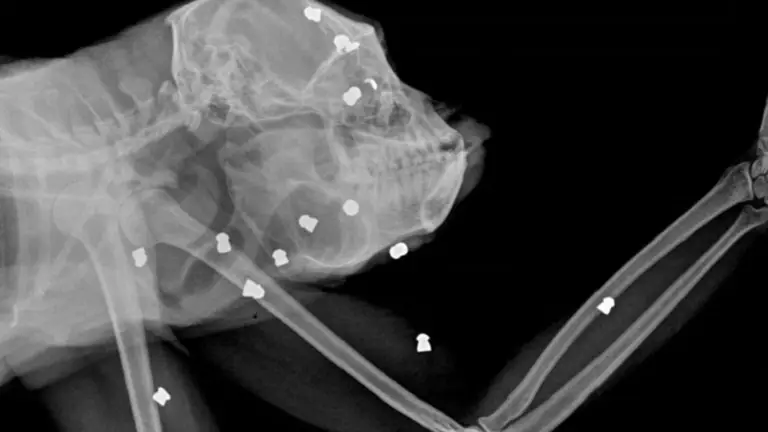

Se le hizo análisis de sangre, estudios oftalmológicos y gracias a las radiografías se constató que tenía 30 balines en todo el cuerpo. Por esta razón, se realizó una cirugía para extraer los perdigones e intentar mejorar su estado clínico. “Lamentablemente no pudimos revertir la situación y con el correr de los días su condición fue desmejorando. Hicimos todo lo que estuvo a nuestro alcance. Esta vez no logramos el objetivo principal de llegar a una liberación, pero no queríamos dejar de contar esta historia, la cual está siendo judicializada por el sufrimiento que padeció el animal”, lamentaron.